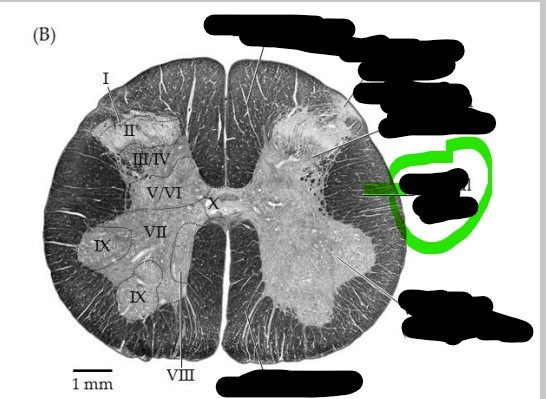

Spinal cord - gray matter

centrally located, and its shape resembles an H or a butterfly; subdivided into anterior horns, lateral horns, posterior horns, and gray commisure

Spinal cord - white matter

external to gray matter and partioned into three regions, posterior, anterior, and lateral funiculus

Spinal cord - dorsal horn

left and right posterior masses of gray matter; axons of sensory neurons and the cell bodies of interneurons located here

Spinal cord - ventral horn

left and right anterior masses of gray matter; primarily house the cell bodies of somatic motor neurons which innervate skeletal muscle

Spinal cord - gray commissure

horizontal bar of gray matter that surrounds the central canal; primarily contains unmyelinated axons and serves as a communication route between the right and left sides of the gray matter

Spinal cord - lateral column

slight protrusion of gray matter of spinal cord into the lateral funiculus of either side; present only in the thoracic and upper lumbar

Spinal cord - central canal

hollow tube that runs the length of the spinal cord; filled with cerebral spinal fluid